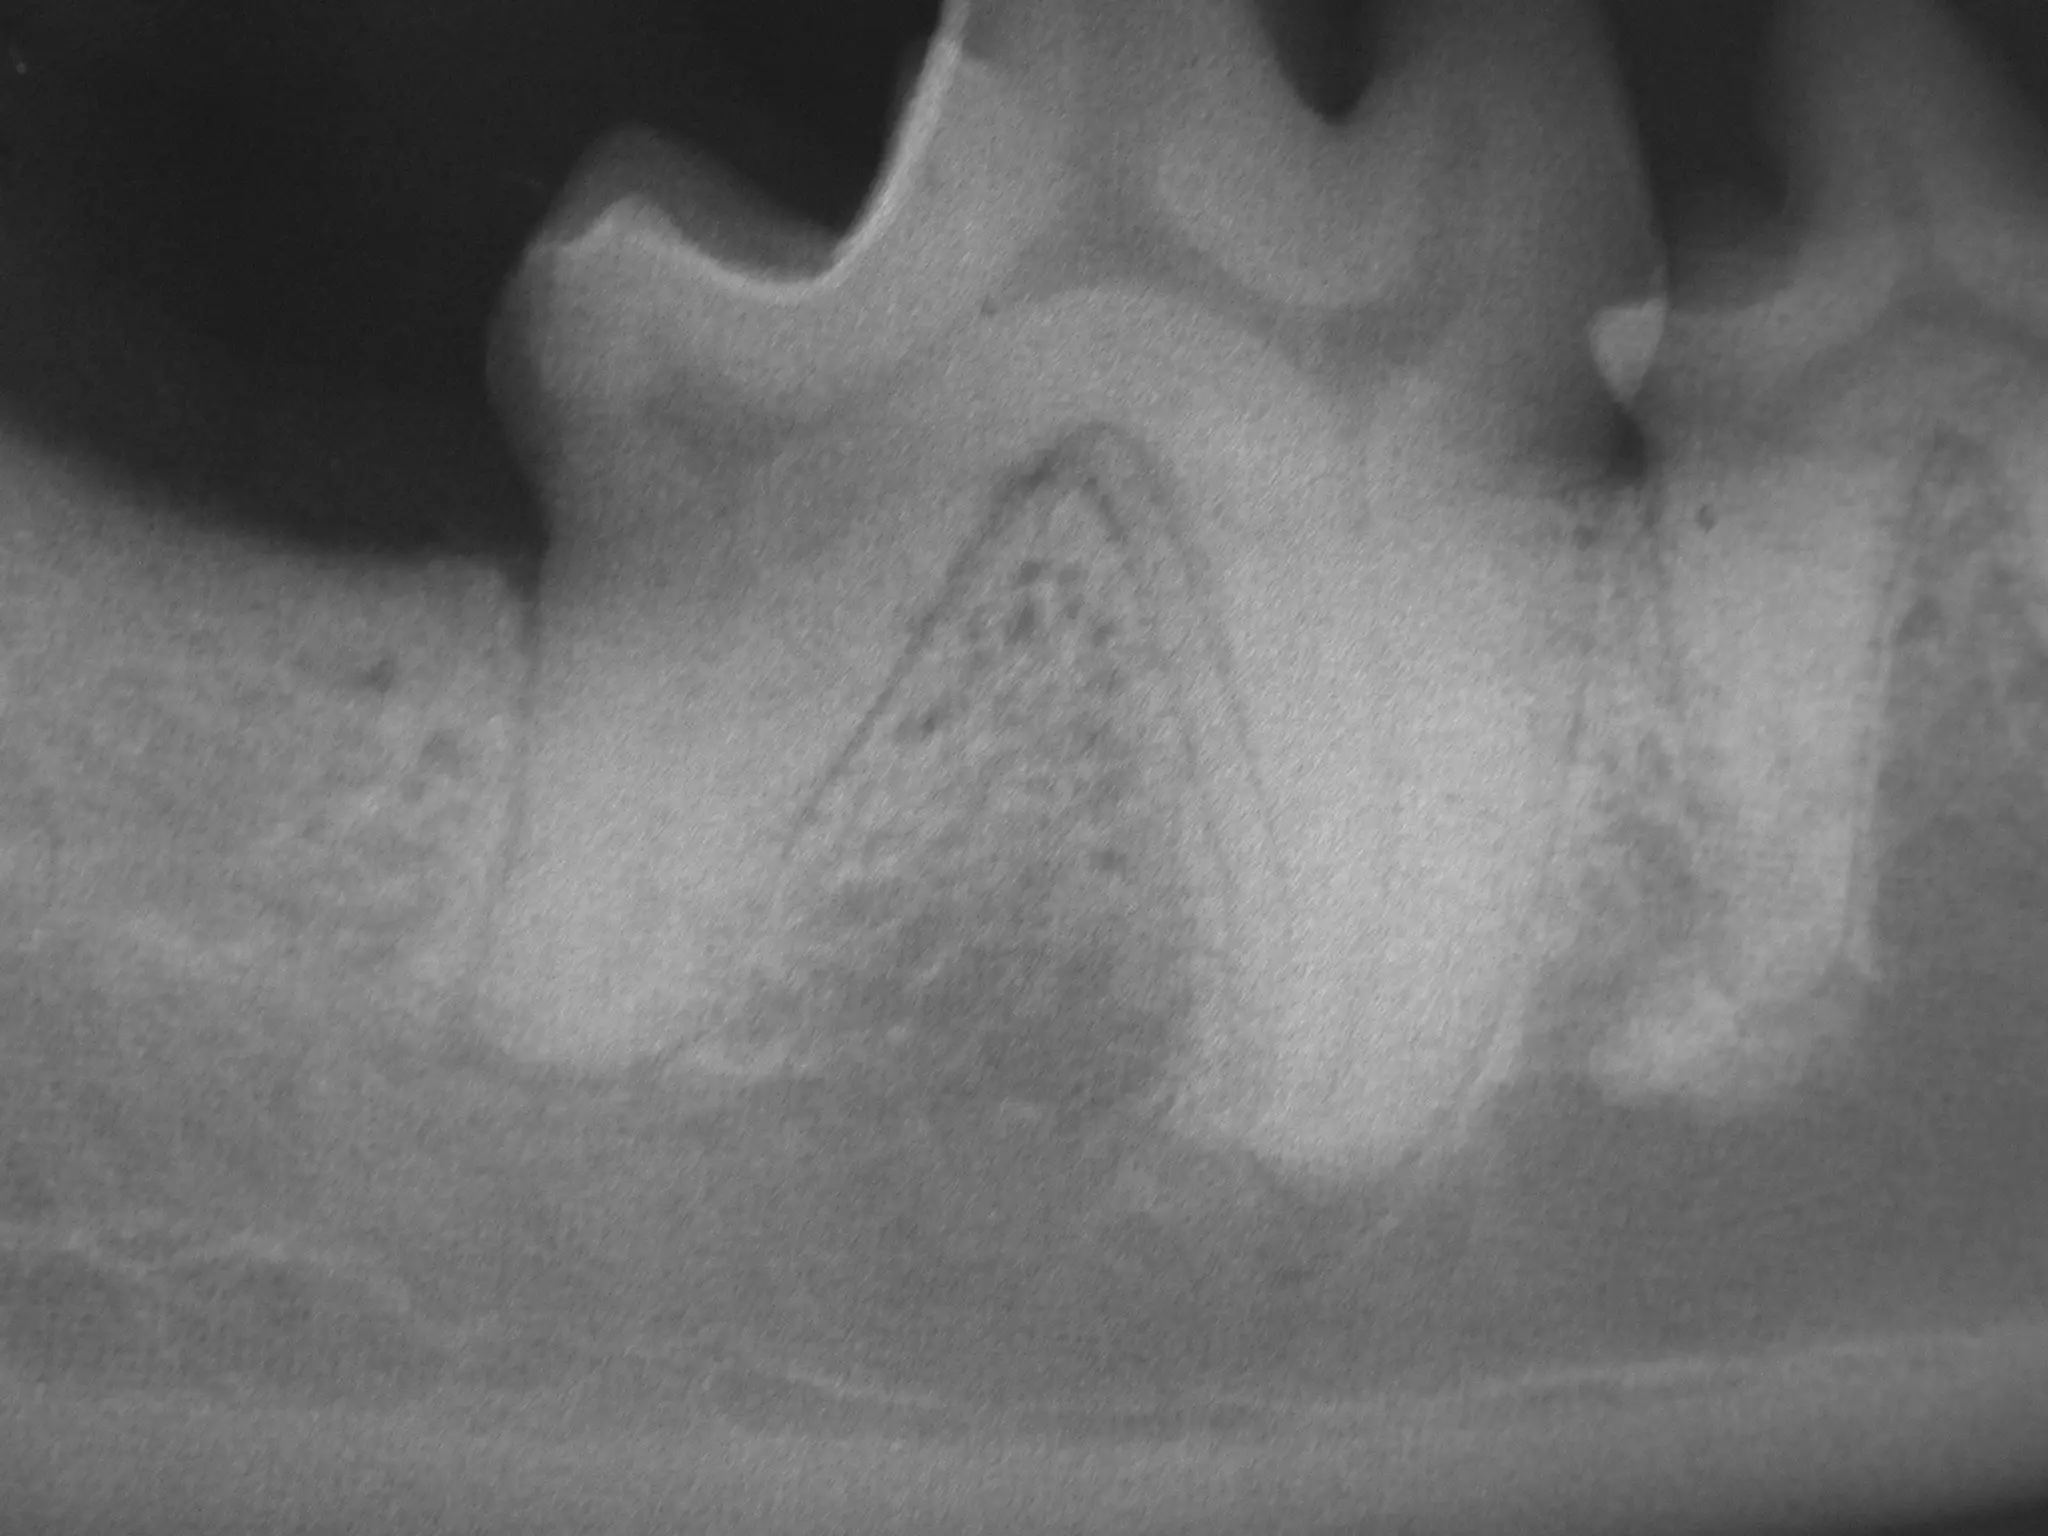

What is the large tooth number in

Triadan?

What process is affecting the area

surrounding this tooth?

34

What is thelarge tooth number in Triadan? What process is affecting the area surrounding this tooth? 34

• #34 ROSTRAL MANDIBULAR (MENTAL) REGIONAL BLOCK The rostral mandibular block infiltrates the rostral extent of the inferior alveolar nerve just before it exits the middle mental foramen. (Figures 6 and 7) The structures anesthetized include the incisors, the canine and the first three premolars. The adjacent bone and soft tissue are also affected. The middle mental foramen is located about 1/3 of the distance from the ventral border to the dorsal border of the mandible at the level of the mesial root of the second premolar. The landmark for infiltration is the mandibular labial frenulum. The frenulum is retracted ventrally. The needle is inserted at the rostral aspect of the frenulum and advanced along the mandibular bone to just enter the canal. If bone is encountered the needle should be backed out and redirected until the needle passes freely into the foramen. Placement can be confirmed by moving the syringe laterally to encounter the lateral aspect of the canal. The patient’s jaw, rather than the alveolar mucosa, will move slightly if the needle is within the canal. The mental nerve block gets the mandibular bone, teeth and soft tissue from the second premolar to the midline. The mandibular labial frenulum is retracted ventrally. The needle is directed into the mesial aspect of the frenulum and advanced against the bone distally to enter the middle mental foramen at the level of the distal frenulum.